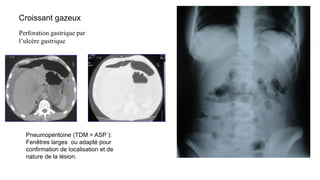

Croissant gazeux

Perforation gastrique par

l’ulcère gastrique

Pneumopéritoine (TDM > ASP ):

Fenêtres larges ou adapté pour

confirmation de localisation et de

nature de la lésion.